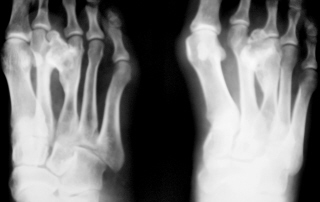

При осмотре правой стопы – иллюстрации 1 и 2 отмечается снижение продольного внутреннего свода стопы, формирование галюс вальгус, с ротацией 1 пальца внутрь, некоторая молоткообразная деформация 3, 4, 5 пальцев. Определяется припухлость стопы по тыльной поверхности, примерно на уровне дистальных отделов 3, 4 плюсневых костей, довольно плотной консистенции, при пальпации умеренно болезненная. На вершине припухлости определяется участок локальной гиперемии розового цвета. Движения пальцев стопы свободные, с некоторой болезненностью в области припухлости.

Иллюстрации 3 и 4 -  определяется тень дополнительного объёмного образования костной плотности, исходящая из дистальной ½ 3 плюсневой кости, растущее  и оказывающее компрессию на 2 плюсневую кость. В дистальном отделе 3 плюсневой кости определяется её уплотнение, утолщение и деформация. Расстояние между 2 и 3 плюсневыми костями увеличено, определяется некоторое расширение щели между основаниями 2 и 3 плюсневыми костями и между клиновидными костями. Определяется сужение суставной щели (по всей видимости компенсаторное) между латеральной клиновидной и кубовидной костями. По наружному контуру 2 плюсневой кости определяется умеренно выраженный периостоз, галюс вальгус, ротация проксимальной фаланги 1 пальца.